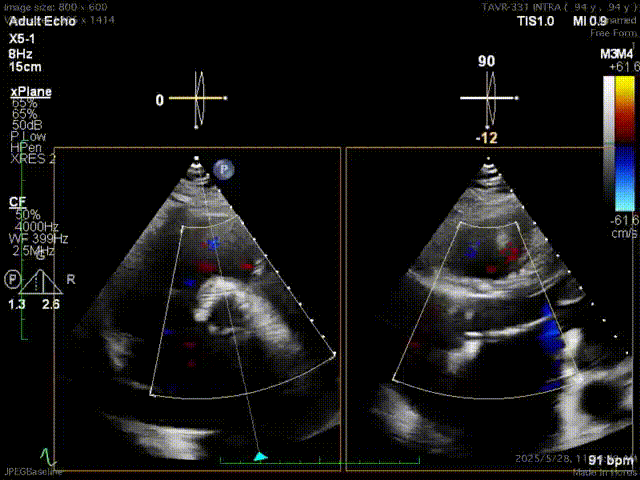

超声显示根部瓣架形态尚好,瓣周6点位置探及轻度反流,遂180bpm起搏下原球囊扩张瓣膜,超声提示瓣周反流减少至微量,瓣叶回声纤细,启闭良好,瓣叶中心未探及确切反流;主动脉瓣跨瓣血流峰值速度约2.4m/s,峰值压差约22mmHg,平均压差约12 mmHg;

球囊后扩后

整个手术过程顺利,团队配合默契,操作精准。术后复查造影显示瓣膜位置满意,形态良好,微量瓣周漏,冠脉显影良好,血流速度正常范围,峰值压差约27mmHg,平均压差约13mmHg。

在植入SAPIEN 3瓣膜后,超声未见明显的返流,狭窄也随之解除,跨瓣压差降低到了12 mmHg,阿婆的心脏终于可以不在高强度的负荷下工作。

此次郭亮教授团队采用经导管主动脉瓣置换术,通过股动脉微创路径完成瓣膜置换,避免了传统开胸手术劈开胸骨的巨大创伤。术中精准释放20mm SAPIEN 3瓣膜,跨瓣峰值压差从 80mmHg降至22mmHg,这不仅重建了心脏泵血通道,更让衰竭的心肌重获“减负”生机。值得一提的是,SAPIEN 3瓣膜以更高的耐用性、强度,和灵活精准的输送系统,为术者保驾护航,助力团队稳定释放瓣膜,展现了创新器械在复杂解剖结构中的精准治疗效果。这场生命的逆转,是技术与仁心的双重见证。